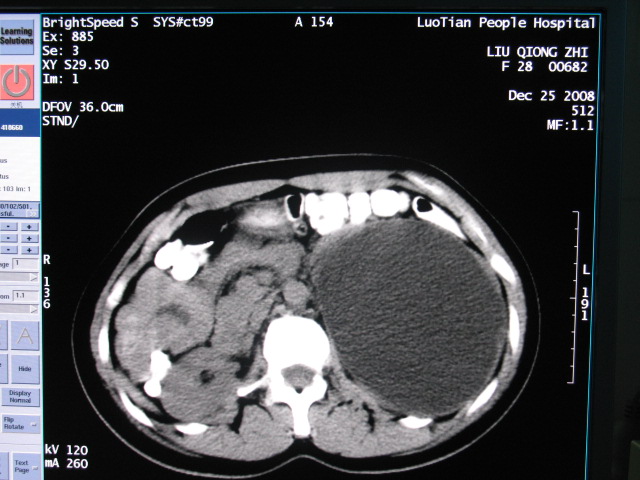

女,28岁,自觉腹部包块一年余

左侧为扩张的输尿管,一直延续到膀胱,那么它的上端应该是扩张的肾盂,但是在他的下方我们看到一个比较正常的肾,所以考虑左侧重复肾盂输尿管畸形。

考虑左侧双肾盂双输尿管畸形,其中一输尿管末端梗阻(不排除异位开口可能)并相应之肾盂及输尿管明显扩张积水。

左侧重复肾、双输尿管畸形。重复肾一般上位肾发育不良,易合并积水。

术后证实是左侧双肾盂双输尿管畸形,巨输尿管巨肾盂症